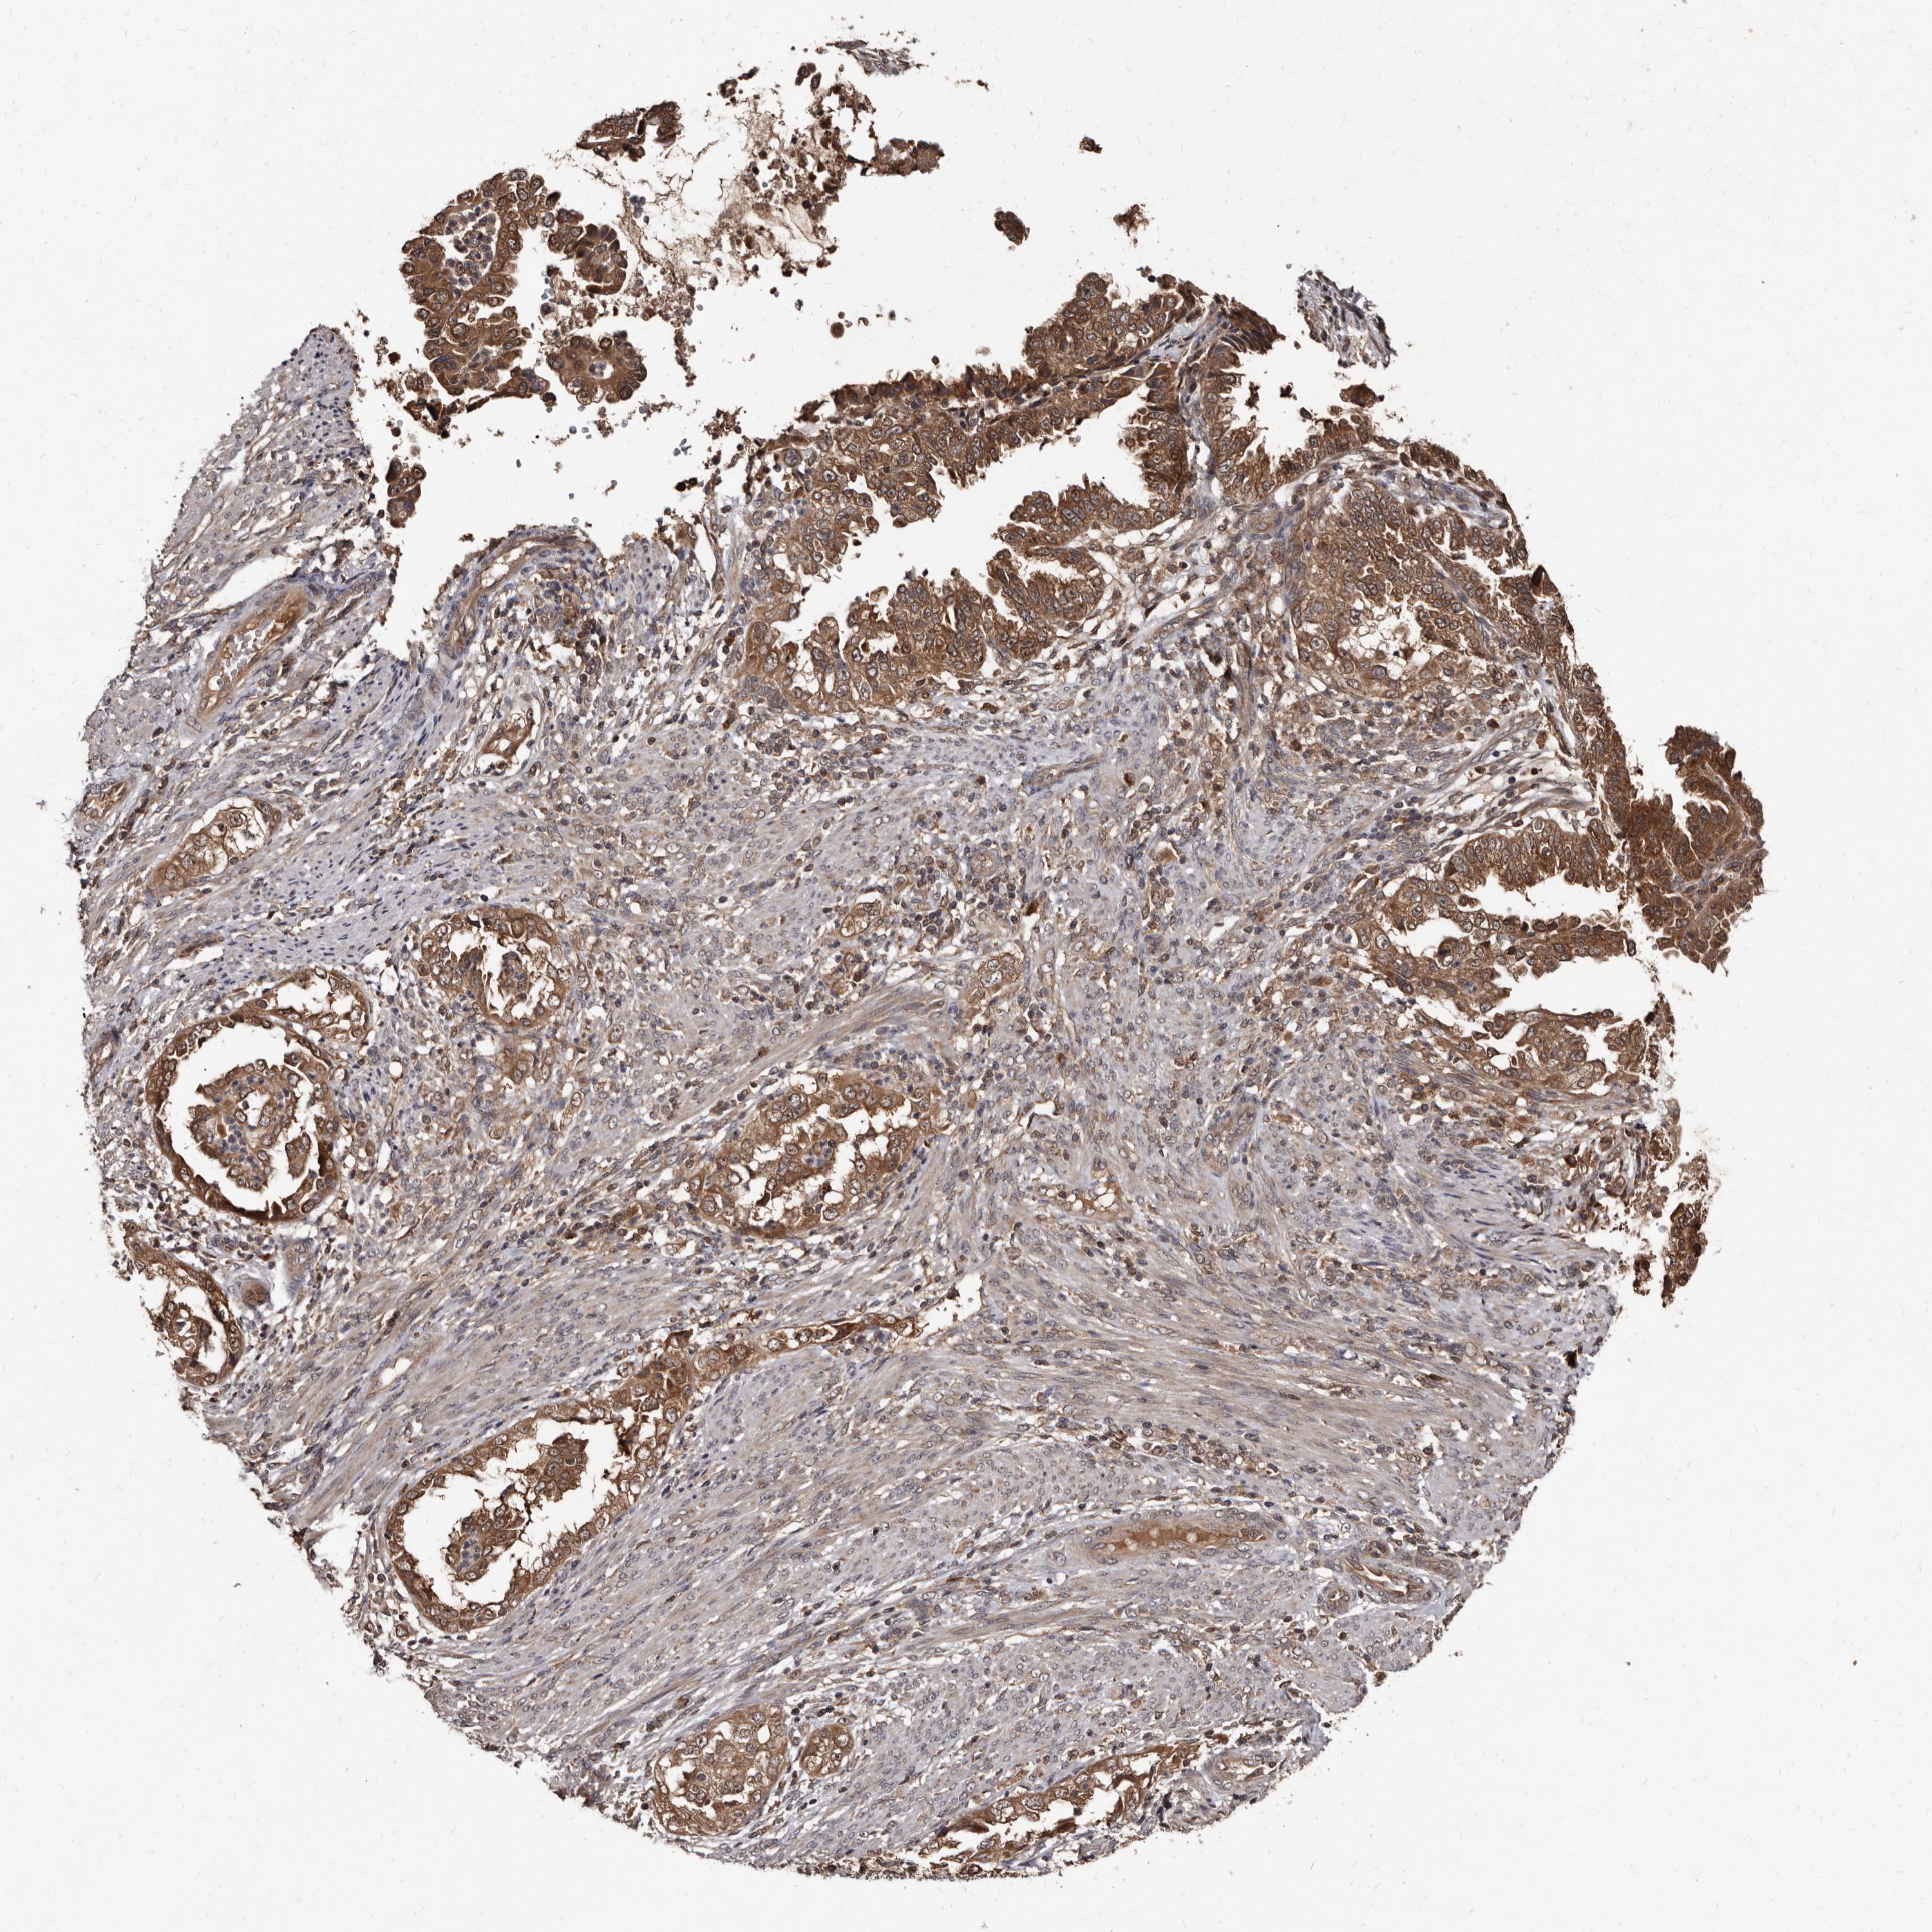

ENDOMETRIAL CANCER - Protein expressioni

A mouse-over function shows sample information and annotation data. Click on an image to view it in a full screen mode. Samples can be filtered based on level of antibody staining by selecting one or several of the following categories: high, medium, low and not detected. The assay and annotation is described here.

Note that samples used for immunohistochemistry by the Human Protein Atlas do not correspond to samples in the TCGA dataset.

Antibody stainingi

Antibody staining in the annotated cell types in the current human tissue is reported as not detected, low, medium, or high, based on conventional immunohistochemistry profiling in selected tissues. This score is based on the combination of the staining intensity and fraction of stained cells.

Each image is clickable and will lead to virtual microscopy that enables deeper exploration of all samples and also displays staining intensity scores, fraction scores and subcellular localization as well as patient and tissue information for each sample.

Antibody HPA029900

Staining

High

Medium

Low

Not detected

Intensity

Strong

Moderate

Weak

Negative

Quantity

>75%

75%-25%

<25%

None

Location

Nuclear

Cytoplasmic/membranous

Cytoplasmic/membranous,nuclear

Adenocarcinoma, NOS

Adenocarcinoma, metastatic, NOS